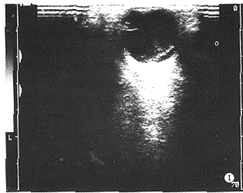

1.原发性部分性视网膜脱离:①玻璃体内出现异常带状高回声,后端连于视乳头,前端 粘附于锯齿缘(图1)。②横向扫查时带状高回声隆起呈弯曲的波浪状或弧形隆起,纵向扫 查时病理带状高回声与眼球壁平行,各径线隆起程度一致(图2)。③转动眼球时,玻璃体 内可见带状高回声轻度震颤或飘浮隆起不一致。④脱离的视网膜带状高回声后面为经裂洞进 入的视网膜下液,前面为玻璃体液。

图1 部分性视网膜脱离,玻璃体无回声区出现带状高回声